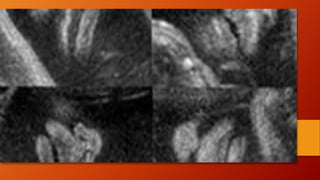

LABIO LEPORINO YFISURA PALATINA • El labio leporino típico aparece como un defecto lineal que se extiende desde el borde superior del labio hasta la fosa nasal Puede estar asociado a fisura palatina, que puede abarcar el paladar blando, el duro, el suelo de la cavidad nasal o incluso el de la órbita. En el 75% de los casos, el defecto es unilateral, y afecta más al lado derecho. • La frecuencia es de 1/800, y en un 50% la alteración aparece de forma asilada (aislada (únicamente labio leporino o fisura palatina) o conjunta. Habitualmente es un hallazgo aislado, pero en un 20% de los casos puede ir asociado a alteraciones genéticas. • Las trisomías 13 y 18 son las más frecuentes. También se ha visto asociado a teratógenos como fármacos antiepilépticos. • El diagnóstico ecográfico se realiza en un corte coronal de la cara, donde en el labio superior se objetiva una zona anecoica, lineal, desde la fosa nasal hasta el labio superior

Para el diagnósticodel paladar hendido se necesitan cortes transversos. Para el diagnóstico del paladar hendido se necesitan cortes transversos.

cortes Corte sagital decara para evaluar perfil del feto. – Morfología de frente, nariz, labios y mentón. Corte coronal (mas importantes), para evaluar integridad facial – A nivel de orbitas para medición de distancia orbitaria – Plano frontocoronal tangencial: nariz, labios, y mentón. Corte transversal: estudio de paladar